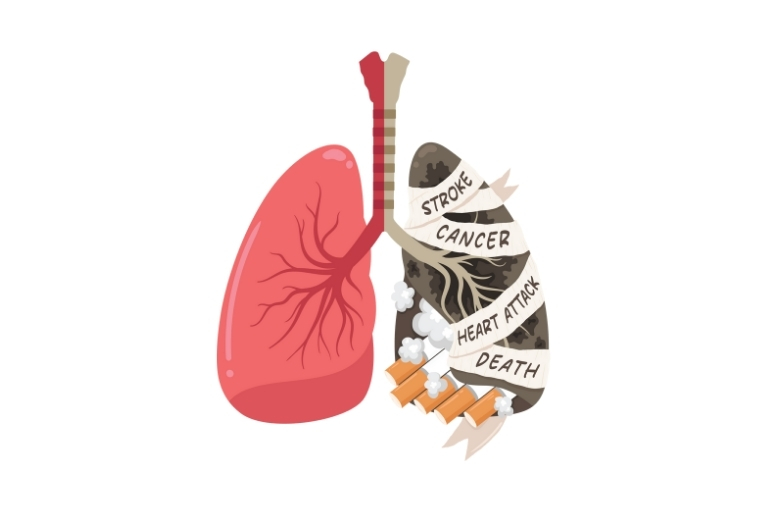

Lung Cancer

Historically, minoritized people are behind in screenings for lung cancer, which is one of the most common and serious types of cancer. We hope you will enjoy using this toolkit, which contains valuable tips and information you can use to become familiar with lung cancer screening and strategies for increasing screenings in your community.